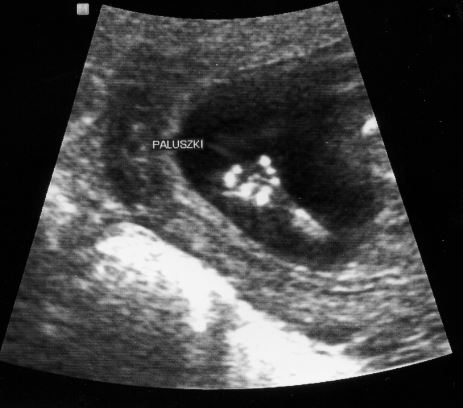

Wreszcie jestem po wizycie - byłam w piątek po południu. Wizyta była prywatna u mojego ginekologa, którego na konsultacje odwiedzam w LuxMed, ale w LuxMed nie ma USG. I bardzo dobrze, że poszłam do mojego lekarza, bo zna moją sprawę, a nie był ograniczony czasowo jak w LuxMed, całe badanie było więc spokojne i bezproblemowe. Przez 40 minut lekarz cierpliwie obejrzał dzieciątko od stóp do głów, opowiadał co widzi, słuchaliśmy serduszko. Na mnie, oczywiście poza widokiem dzieckawrażenie zrobiły miny męża, do którego pewnie dopiero teraz dotarło, że to naprawdę jest już malutki człowieczek a nie jakiś krewetkopodobny robaczek. Na samym początku bejbik trzymał się rączkami za pępowinę, potem też podawał sobie ręce, raz pomachał, niesamowite przeżycia

Jeśli chodzi o jakieś konkretne wymiary i cyferki to ich teraz nie podam bo nie mam ich przy sobie. Pamiętam tylko, że przezierność wyszła ok 1.0, co jest podobno rewelacyjnym wynikiem, a dziecko zgodnie z wymiarami na USG jest o kilka dni starsze (zamiast 12t5d wychodzi 13t3d czy jakos tak i zamiast 20 kwietnia wychodzi 15 kwietnia), ale trzymam sie tego co pisała marcia - że bardziej liczy się pierwsze USG i data OM. W każdym razie cieszę się niezmiernie, że dzieciątko się super rozwija i na razie rośnie sobie zdrowo. Spadł mi ogromny kamień z serca i dzięki temu z większą pewnością i nadzieją na powodzenie zaczynam II trymestr.

Aha i jeszcze fotki

Zobacz załącznik 587852Zobacz załącznik 587853